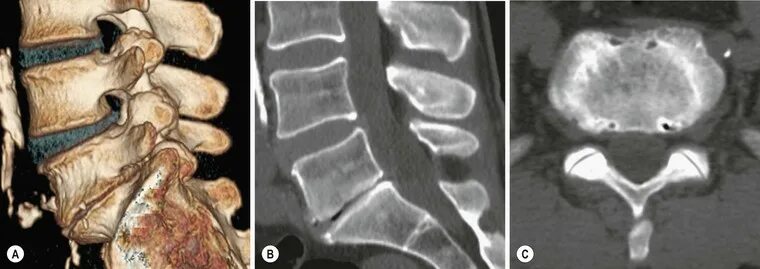

Спондилоартроз l4 s1 сегментов